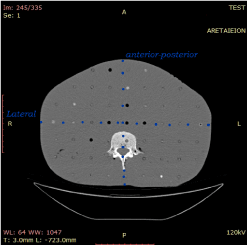

The Size-Specific Dose Estimate (SSDE) is a recently proposed dose index to quantify the dose received by a patient during a scan, by taking into account the patient’s size as well [13]. It is based on a series of published conversion factors by the AAPM that takes into account the patient’s size and is applied to the displayed CTDIvol. Transverse CT images should be used to estimate patient size since localizer radiographs generally overestimate patient size due to magnification. Measurement of patient size can be obtained from the mid-slice location on the transverse CT image series [18].

The conversion factors are divided in those concerning either head scans (based on the 16 cm diameter head dosimetry phantom) or body scans (based on the 32 cm diameter body dosimetry phantom) [13]. The patient size is taken into account by considering one of four possible measurements: the patient’s lateral (LAT) dimension (left-to-right dimension of the body part being scanned), the anterior-posterior (AP) dimension (thickness of the body part being scanned), the sum of the LAT and AP dimensions or the effective diameter. The effective diameter (Eff-D) can be thought as the diameter of the circle whose area is the same as that of the patient cross section [13]. It can be calculated as:

Figure 2. The documented dimensions from a CT scan, needed to calculate the Effective Diameter (Eff-D) of each patient. Rando Phantom transverse slice is displayed to show the AP and LAT measurements